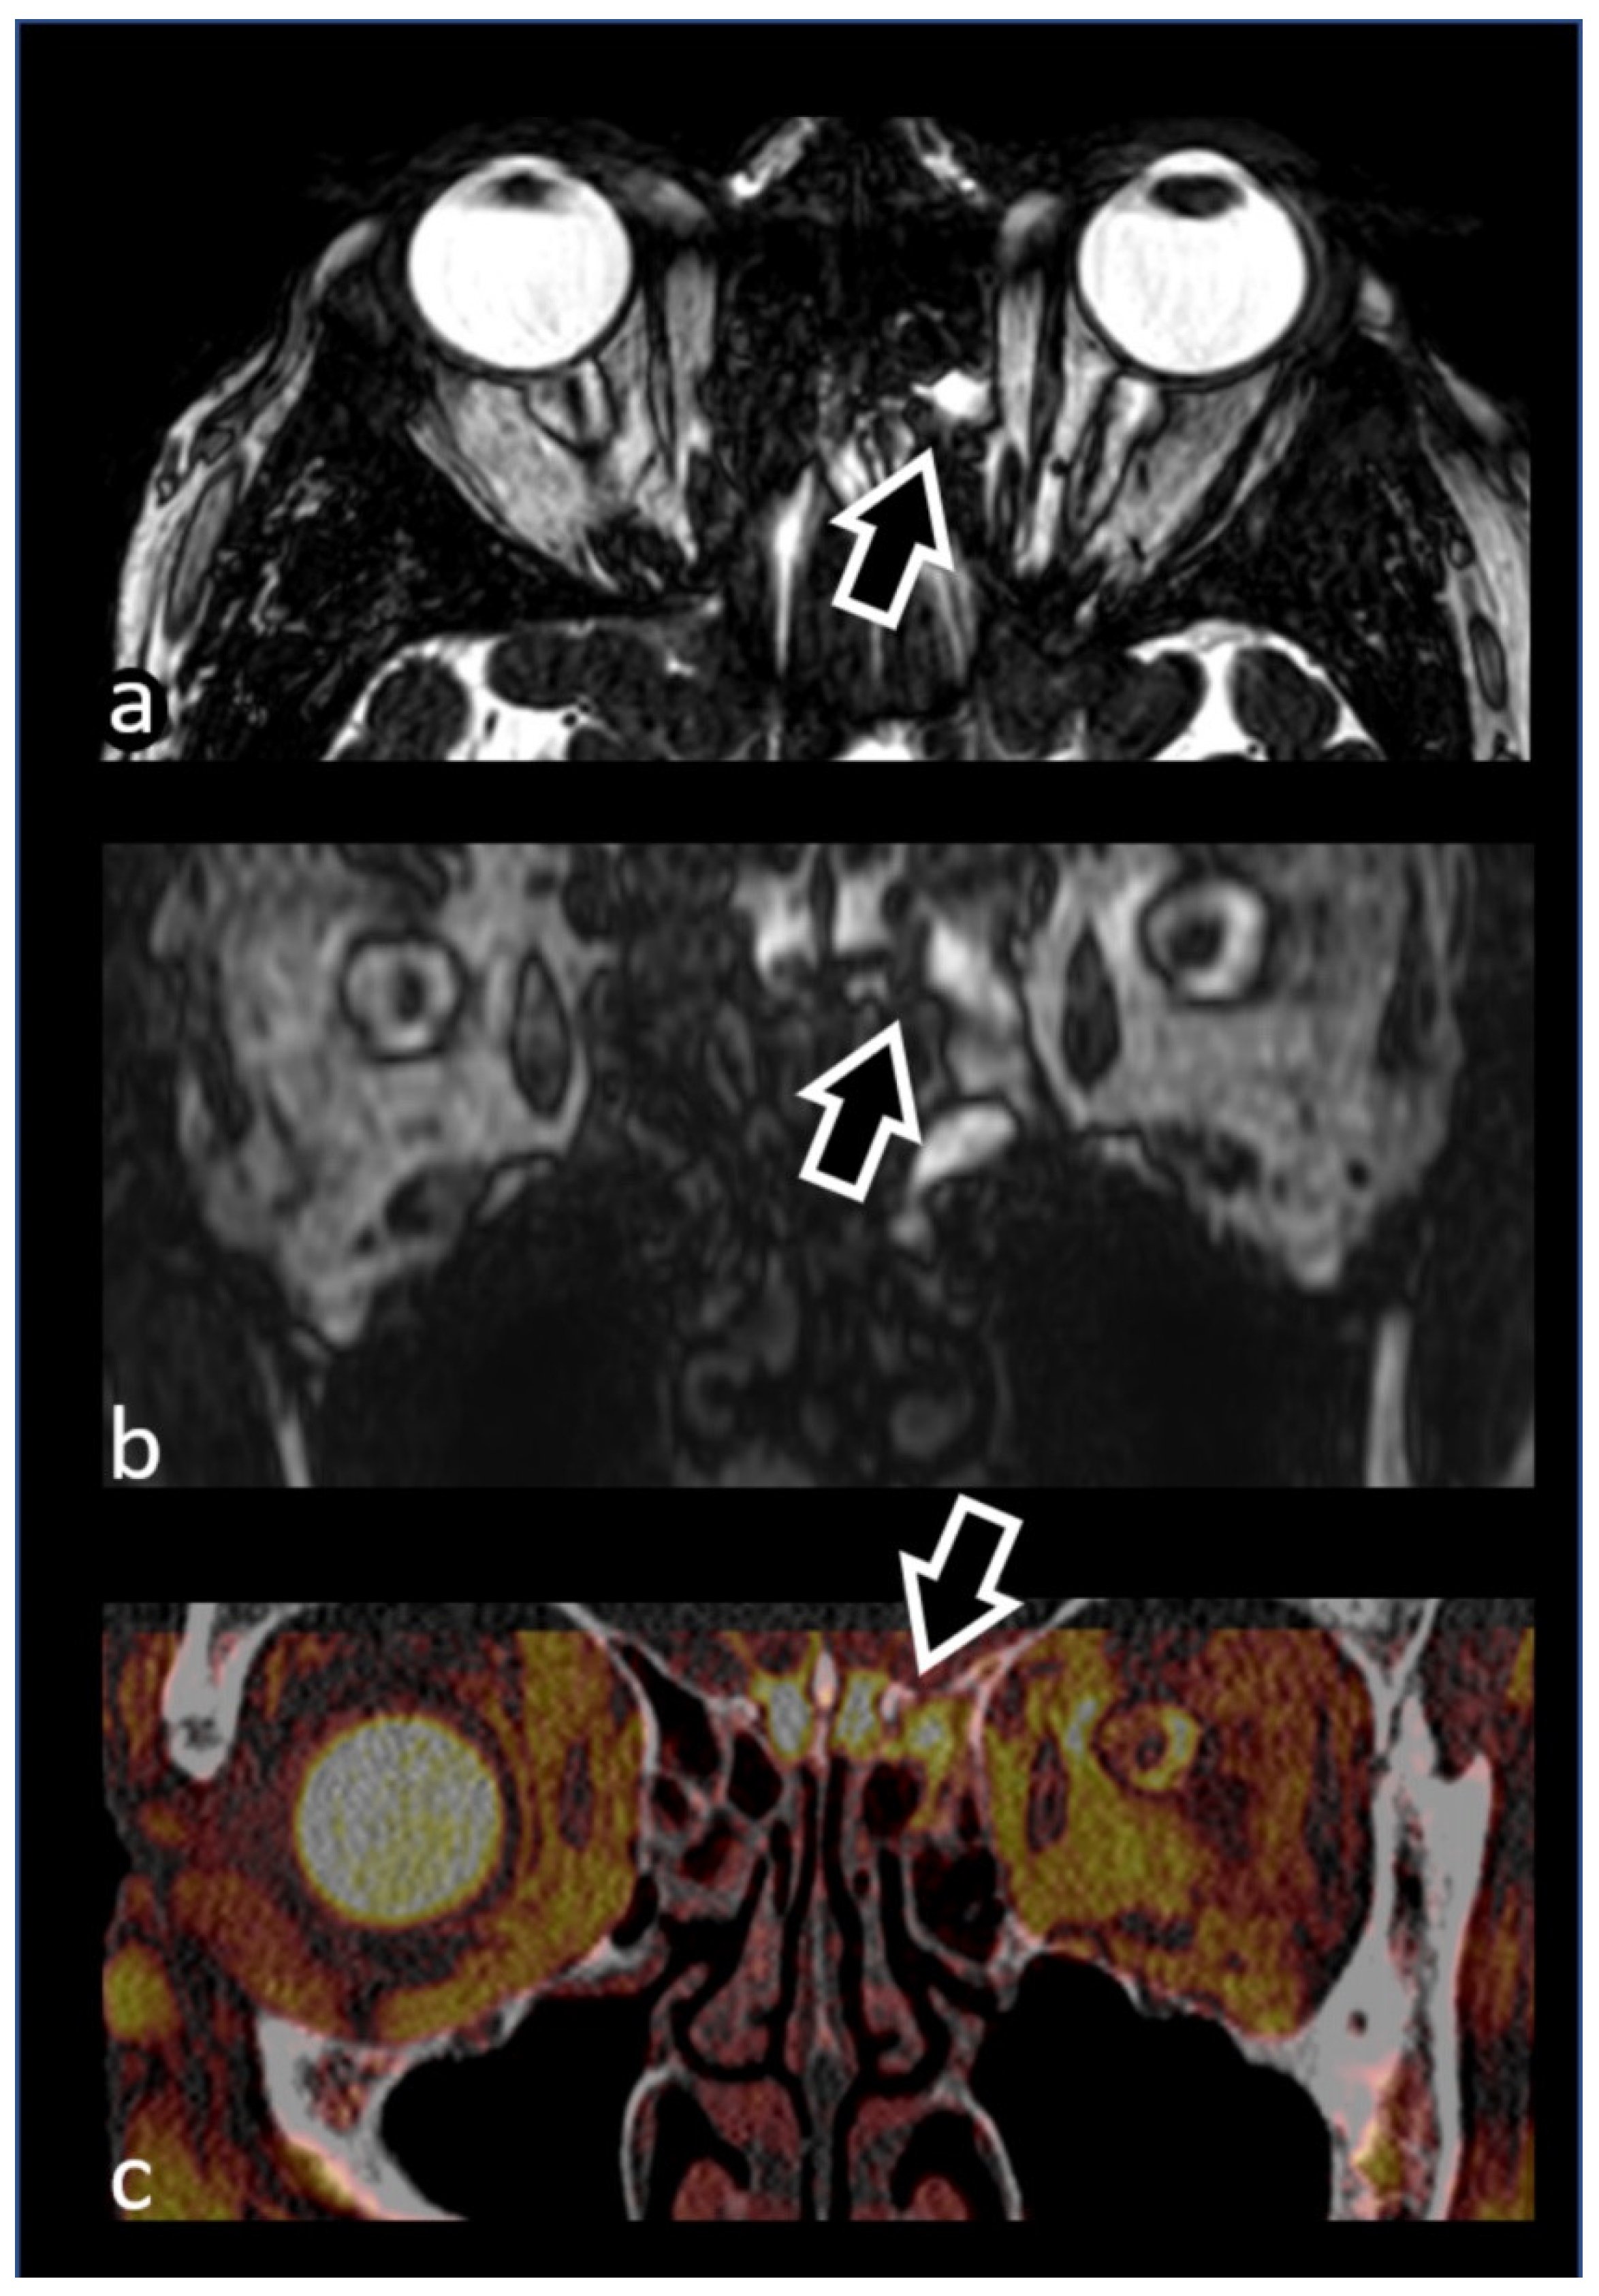

- Mormina, E.; Caragliano, A.A.; Tessitore, A.; Cavallaro, M.; Buonomo, O.; Visalli, C.; Pitrone, A.; Velo, M.; Galletta, K.; Longo, M.; et al. Fusion of magnetic resonance angiography and cisternography in acute ischemic stroke reveals the vessel anatomy ahead of the clot: A technical note to see beyond obstacles. Neuroradiology 2022, 64, 1457–1460. [Google Scholar] [CrossRef]

- Mormina, E.; Tessitore, A.; Cavallaro, M.; Caragliano, A.A.; Buonomo, O.; Longo, M.; Granata, F.; Caponnetto, M.; Vinci, S.L. Magnetic Resonance Angiography and Cisternography fused images in acute ischemic stroke may save time during endovascular procedure revealing vessel anatomy. Heliyon 2022, 8, e10288. [Google Scholar] [CrossRef] [PubMed]